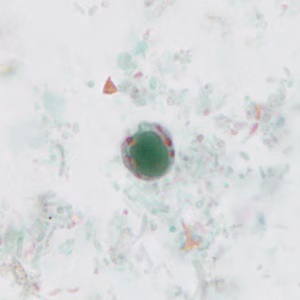

Several people developed gastrointestinal symptoms of watery diarrhea, nausea with vomiting, and low-grade fever approximately 1 week after attending a catered event. Stool specimens were collected for laboratory testing which included a formalin-ethyl acetate concentration with brightfield wet mount examination.